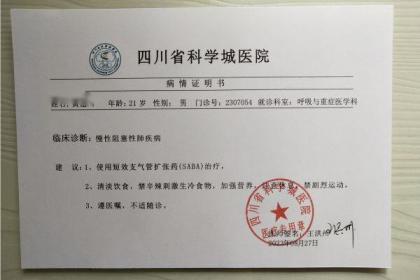

武汉惠鑫健康管理有限公司专业代开上海医院病历证明17267193882,诊断证明,医院病假条、病假单、请假条、病例单,医院休学证明、免军训证明、免体测证明,化验单、CT报告单、B超单、病理报告、心电图,三甲医院病例诊断证明、医院住院证明、医院出院证明,医院怀孕证明、结扎上环证明、流产引产证明,医院病危通知书、医院全套病历等等。长期与市区各大三甲医院保持良好关系,欢迎随时联系我们!

医院病假单主要就是由医生开取的一个关于身体的病状情况,在严重的情况下要请假休息才行。很多人在请假的时候不知道怎么开医院病假条,请直接联系我!只有写好医院请假条才能使自己在家里安心养病,休假也是为了自己的身体健康尽快恢复。医院一般不可以直接开病假条,但是经正规医院的医师检查后,可以为病人开具疾病诊断书、健康证明书等材料,而劳动者可以携带该材料去申请用人单位开病假条。

总之,现在很多情况都会要求开具各种各样的医院病历证明,譬如公司请病假,怀孕休假,学校办休学,免军训,免体免测等等。什么情况才能开具诊断证明?复杂也好,难办也好,放轻松一点,我们愿意为您代劳!